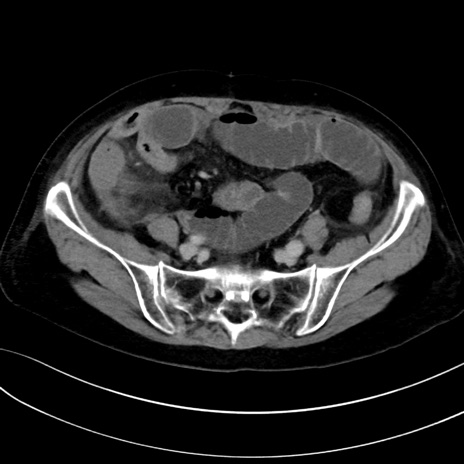

症例13 CT(横断像)1日半後